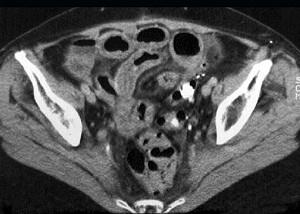

问题 女,54岁,直肠癌放疗后一月,阵发性腹痛腹胀,呕吐应,CT表现如图,应诊断为 ( )

选项 A.小肠淋巴瘤 B.小肠结核 C.小肠Crohn病 D.放射性小肠炎 E.肠易激综合征

答案 D